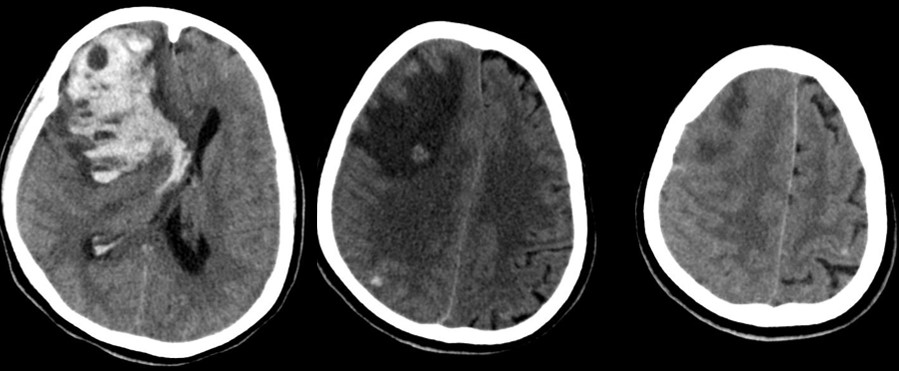

Neurological disease: Approximately 15–20% of hospitalized patients develop altered mental status or more focal symptoms. Imaging is positive in a minority, however. Ischemic infarcts are the most common imaging findings, probably related to coagulopathy. Reported infrequently are hemorrhagic stroke, cranial nerve inflammation, encephalopathy, and worsening of multiple sclerosis plaques.